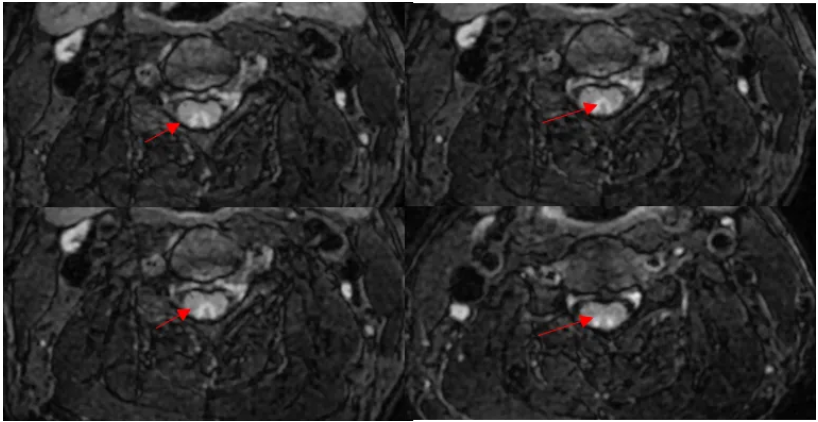

很简单。 椎间盘突出。 想看清椎间盘突出,最好用的序列莫过于横断面梯度回波序列T2*WI MERGE(multiecho recalled gradient echo,多回波的梯度回波序列)。与常规T2WI FSE序列相比,其优点在于脑脊液流空伪影很少。所以,脑脊液呈显著高信号,突出的椎间盘呈低信号,二者之间对比差异很大,图像效果杠杠滴。

小编以后也要注意脊柱大保健了(写到此处,小编无意识地活动了一下脖子)。 横断面T2*WI 梯度回波序列还有一个特点,脊髓的小蝴蝶显示比较好。 感觉这个患者小蝴蝶显示很一般啊。 这个垃圾机器。曾经有个教授的课件,小蝴蝶可漂亮了。。。 再翻一遍图像,好像脊髓怪怪的。

五、综合诊断 脊髓亚急性联合变性(SCD) v由于维生素B12的摄入、吸收、结合、转运或代谢障碍导致体内含量不足而引起的中枢和周围神经系统变性的疾病。 v主要累及脊髓后索、侧索及周围神经,影像表现为倒置的“V”。 追问病史,该患者有长期大量饮酒史,胃功能受损